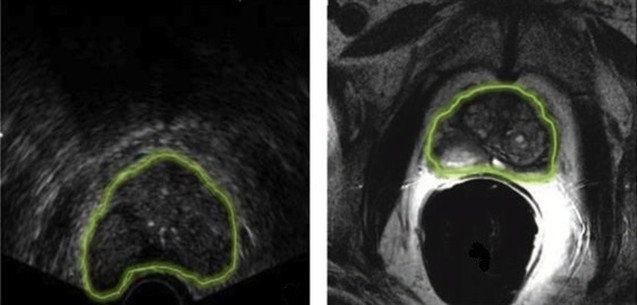

Το διορθικό υπερηχογράφημα του προστάτη (TRUS, Transrectal ultrasonography) είναι μια διαγνωστική εξέταση για την απεικόνιση του προστάτη αδένα και των γύρω περιοχών.

Η εξέταση αυτή παρέχει ακριβείς πληροφορίες για το μέγεθος και τη δομή του αδένα, την ύπαρξη φλεγμονών, υπερτροφίας ή «ύποπτων» περιοχών που μπορεί να υποδεικνύουν καρκίνο. Χρησιμοποιείται και ως οδηγός για βιοψία προστάτη. Κατά τη διάρκεια των βιοψιών προστάτη, το διορθικό υπερηχογράφημα μπορεί να ανιχνεύσει μια δυνητικά ύποπτη υπόηχη περιοχή. Το υπερηχογράφημα όμως από μόνο του δεν αποτελεί αξιόπιστη διαγνωστική εξέταση για κακοήθεια του προστάτη.

Η μαγνητική τομογραφία του προστάτη (mpΜRI, multiparametric magnetic resonance image) έχει πολύ καλύτερη ανάλυση μαλακών ιστών από το υπερηχογράφημα. Μπορεί να εντοπίσει περιοχές στον αδένα που είναι πραγματικά ύποπτες με υψηλό βαθμό ακρίβειας και αξιοπιστίας (θετική προγνωστική αξία μεγαλύτερη από 90%).